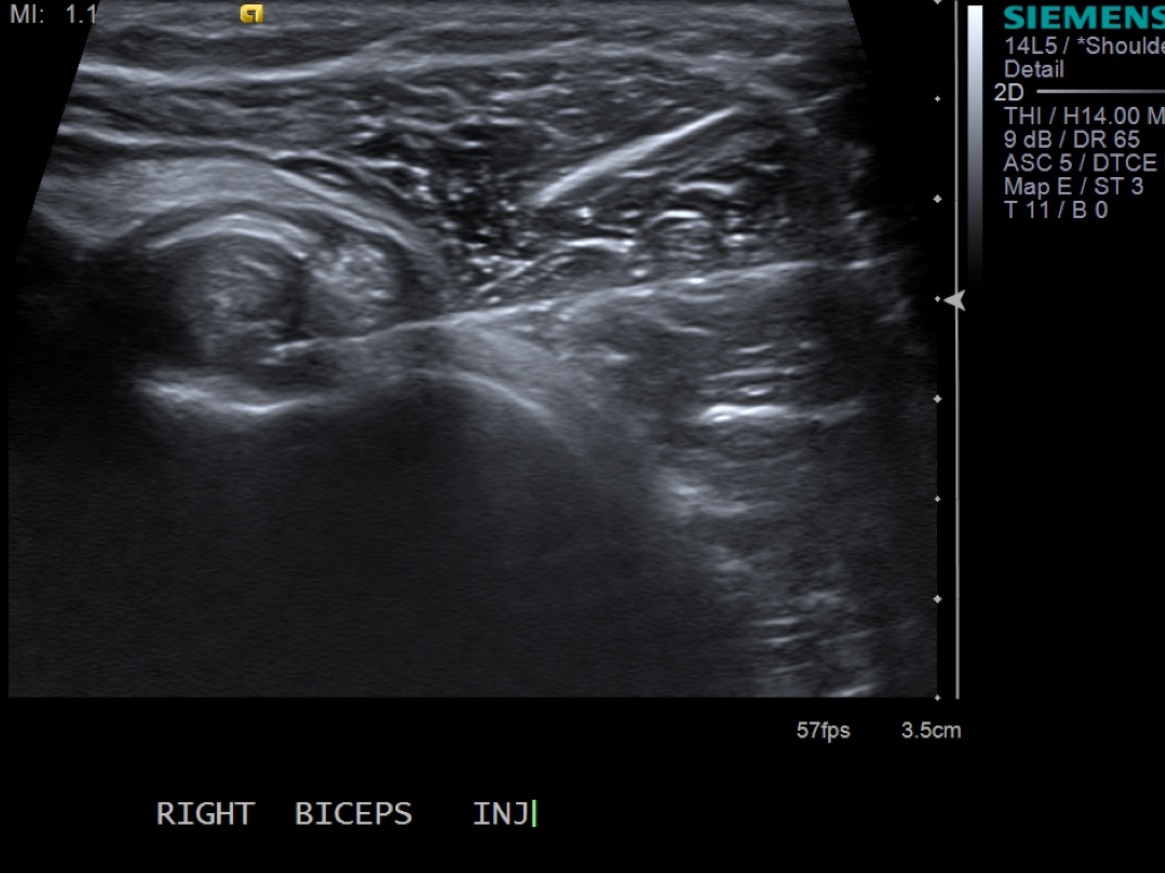

10. With ultrasound guidance, advance the 25g needle into the sheath surrounding the tendon.

• descriptiondescription

11. Test inject to see if easy flow with 1% lidocaine. If no resistance and see distention of the tendon sheath, exchange for 3cc syringe with injectable steroid and ropivacaine.